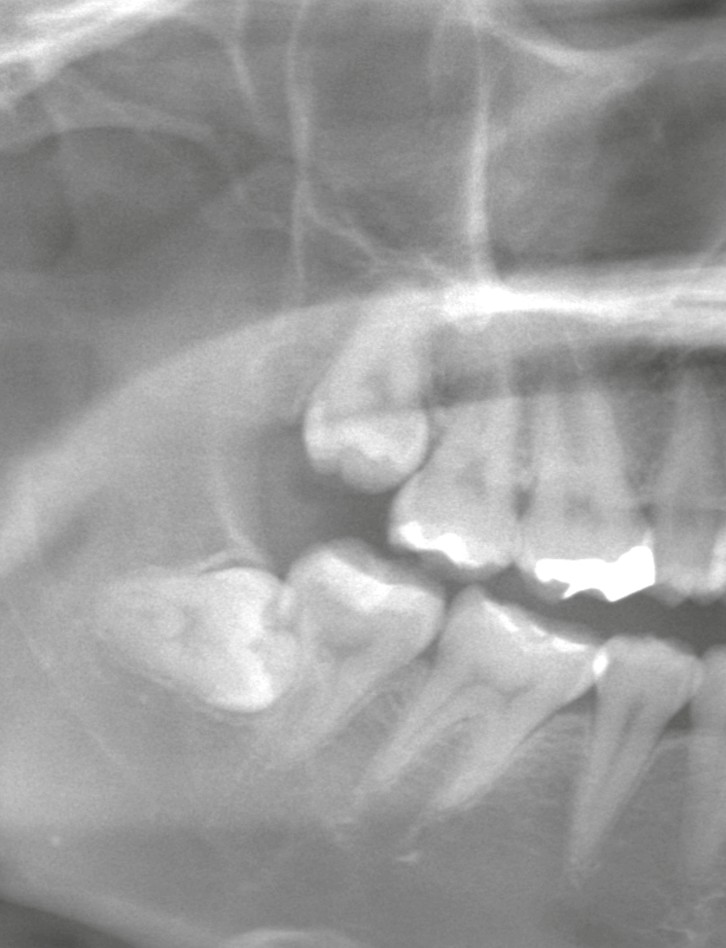

この症状の主な原因は、

抜歯によって隣の歯の根面が露出することにあります。

親知らずが隣の歯に接していた場合、

これまで歯肉や骨に覆われていた部分が、抜歯後に一時的に露出します。

この部分はエナメル質ではなく、

刺激に対して敏感な象牙質で構成されているため、